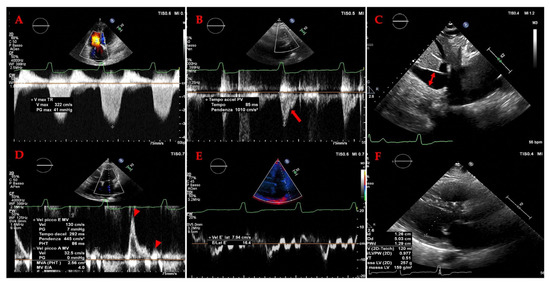

Long-Term Follow-Up of Professional Soccer Players: The Analyses of Left and Right Heart Morphology and Function by Conventional, Three-Dimensional, and Deformation Analyses

Background: Transthoracic echocardiography (TTE) is the primary imaging modality to assess cardiac morphology and function. In athletes, distinguishing physiological adaptations from pathological changes is essential. This study aimed to evaluate long-term cardiac structural and functional changes in professional soccer players. Methods: This retrospective [...] Read more.

Background: Transthoracic echocardiography (TTE) is the primary imaging modality to assess cardiac morphology and function. In athletes, distinguishing physiological adaptations from pathological changes is essential. This study aimed to evaluate long-term cardiac structural and functional changes in professional soccer players. Methods: This retrospective study included 20 healthy male professional soccer players (mean age 21.2 ± 3.4 years) from the German first division, examined annually from 2016 to 2024 (mean follow-up 5.6 ± 2.0 years). TTE parameters associated with the “athlete’s heart” were assessed, including left ventricular end-diastolic diameter (LVEDD), interventricular septal thickness (IVSD), relative wall thickness (RWT), indexed LV mass (LVMi), and left atrial volume index (LAVi), along with 3D-derived LV and RV volumes. Advanced deformation imaging included global longitudinal strain (GLS), right ventricular strain (RVS), and left/right atrial reservoir strain (LASr and RASr, respectively). Baseline and final follow-up values were compared. Results: No significant changes were observed over time in conventional or advanced echocardiographic parameters (e.g., LVEDD: 54.5 ± 3.1 mm vs. 54.6 ± 3.9 mm; p = 0.868; GLS: −18.7% ± 2.2% vs. −18.4% ± 1.9%; p = 0.670). Ventricular volumes and strain values also remained stable throughout follow-up. Conclusions: Over a mean follow-up of more than five years, professional soccer players showed stable cardiac morphology and function without evidence of pathological remodeling. These findings support the concept that long-term high-level training in mixed-discipline sports leads to balanced, physiological cardiac adaptation. Full article